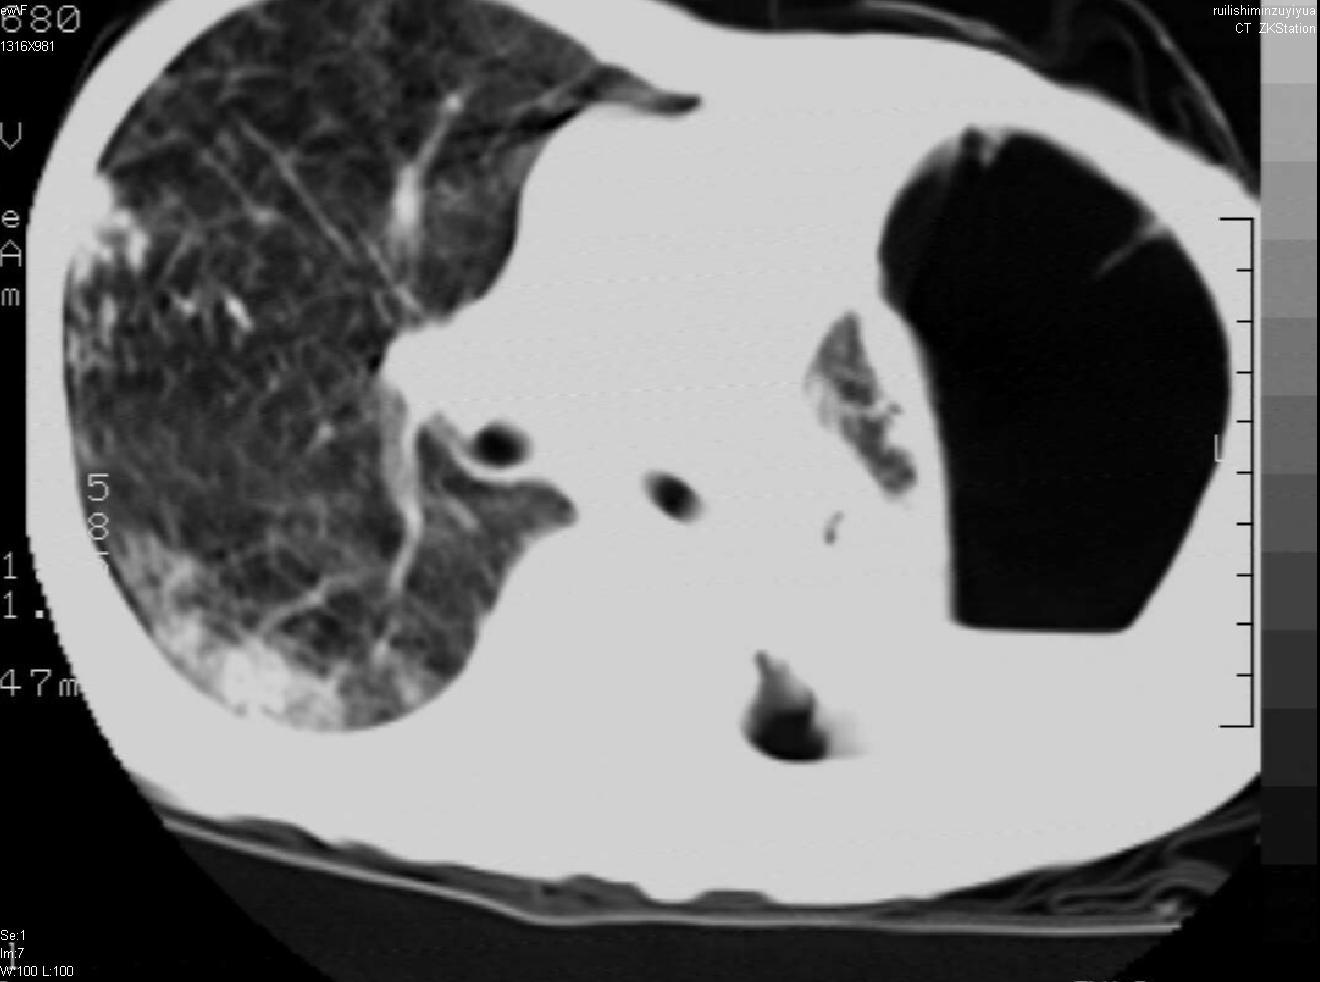

以下是引用天南地北在2007-6-11 23:32:00的发言:[br]1:左侧肺毁损(结核性)伴感染(多发空洞伴液平面)。[br]2:右肺继发型肺结核。

以下是引用avril在2007-6-12 1:17:00的发言:[br]1、左肺毁损。[br]2、左肺多发肺大泡伴自发性气液胸形成。[br]3、右肺继发型结核。

以下是引用尚峰在2007-6-11 22:44:00的发言:[br]慢阻肺、肺纤维化、肺大泡、气胸形成,此患者有没有急性病史?